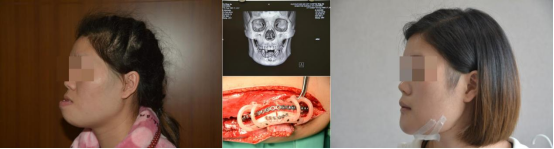

1、复杂牙、多生牙及各种埋伏智齿微创拔除。牙槽外科、口腔颌面创伤及口腔颌面部肿瘤的诊断及治疗,显微外科及颌面部软硬组织缺损的数字化修复重建。

3、口腔颌面创伤和骨折的诊断和序列治疗。

5、口腔颌面部显微外科和颌面部软硬组织缺损的数字化修复重建。